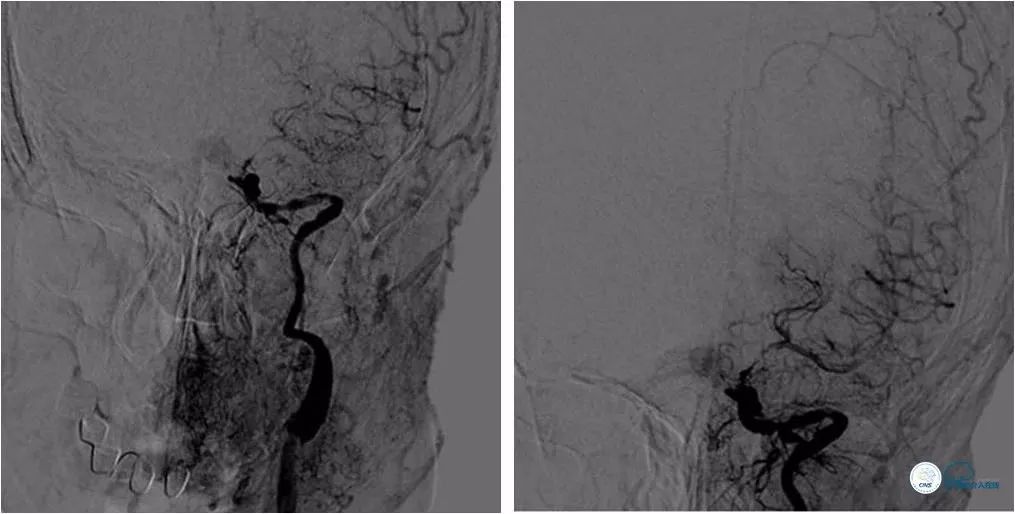

全麻下右股动脉入路,8F导引导管至左颈总动脉末端,将6F Navien导管送至左颈内动脉C1段以远,造影示左颈内动脉C6-7段长段狭窄,狭窄率约90%,长度约10mm(图7)。

图7

路径图下沿Navien导管送入Echelon 10微导管携Synchro微导丝(0.014″,200cm)尝试过狭窄段未成功(图8)。

图8